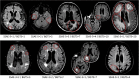

Introduction: Amyloid-related imaging abnormalities-edema (ARIA-E) is associated with anti-amyloid beta monoclonal antibody treatment. ARIA-E severity may be assessed using the Barkhof Grand Total Scale (BGTS) or the 3- or 5-point Severity Scales of ARIA-E (SSAE-3/SSAE-5). We assessed inter- and intra-reader correlations between SSAE-3/5 and BGTS.

Methods: Magnetic resonance imaging scans were collected from 75 participants in the SCarlet RoAD and Marguerite RoAD studies. Three neuroradiologists reviewed scans at baseline and at follow-up. Concordance in dichotomized ARIA-E ratings was assessed for a range of BGTS thresholds.

Results: SSAE-3/5 scores correlated with BGTS scores, with high inter-reader intraclass correlation coefficients across all scales. There was high agreement in dichotomized ratings for SSAE-3 > 1 versus BGTS > 3 for all readers (accuracy 0.85-0.93) and between pairs of readers.